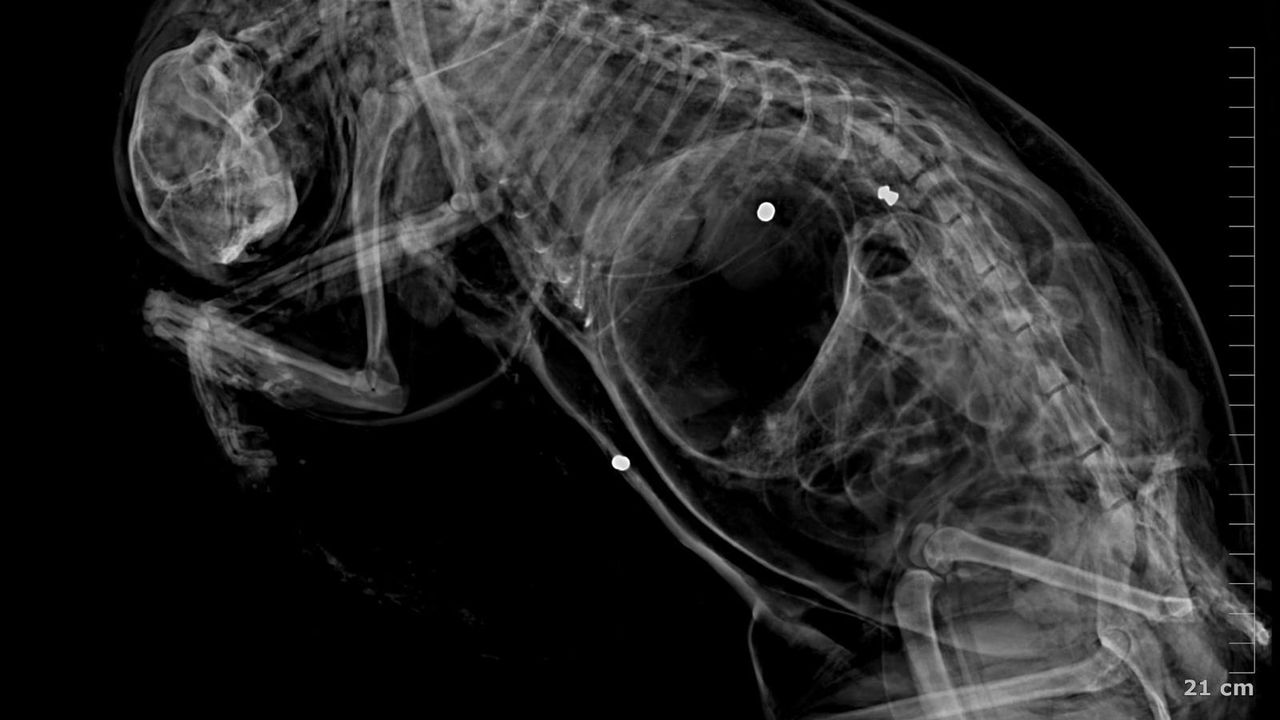

İpsala Cumhuriyet Başsavcılığı'nın olaya ilişkin hazırladığı iddianamede K.G., hakkında, 'Bir ev hayvanını veya evcil hayvanı kasten öldürme' suçundan 6 aydan 3 yıla kadar hapis cezası istendi. İddianamede, "Herhangi bir silah ateşleme görüntüsü tespit edilmese de şüphelinin ikamet ettiği evin bahçe kapısı önünde bir kedinin can çekiştiği ve bir kedinin de kaçtığının tespit edildiği, dosya kapsamında tanık olarak beyanı alınan S.Ç.'nin şüphelinin bahçe kapısı önünde bir kediyi yatar vaziyette gördüğünü, başını sevmek istediğinde kedinin ölü olduğunu fark ettiğini, kediyi eline aldığında başından kan aktığını görmesi üzerine yol üzerinde kalmaması amacıyla kediyi çöp tenekesinin içerisine bıraktığını, ölen ve yaralanan 2 kedi hakkında düzenlenen 25/08/2025 tarihli veteriner hekim ön muayene raporu ile çekilen radyografilerde ateşli silah yaralanması (kuş saçması) ile uyumlu patolojiler gözlemlendiği şeklinde rapor tanzim edildi. Tüm dosya kapsamı incelenmekle şüpheli savunması, bilgi sahibi beyanları, İpsala İlçe Tarım Müdürlüğü'nün yazılı başvurusu, müşteki beyanı, kamera görüntüleri ve kriminal raporları birlikte değerlendirildiğinde, şüphelinin olay tarihinde müşteki Hüseyin Bülbül tarafından da beslenmekte olan sokak kedilerine ateş etmek suretiyle, bir kedinin ölümüne neden olarak üzerine atılı suçu işlediğine dair ve bir kedinin yaralanmasına neden olarak tariflenen suçu işlediğine dair hakkında kamu davası açmak üzere yeterli şüphe oluşturacak kadar delilin mevcut olduğu anlaşılmakla" denildi.

K.G.'nin kedileri bahçesinde ateşli silah ile vurduğunu belirten Ürkmez, "Bununla ilgili delillerimizi dosyayla sunmuş bulunmaktayız. Onun haricinde veteriner ön raporunda da kedilerin ölümüyle ilgili olarak vücutlarında saçma bulunduğu açıklığa kavuşmuştur. Kamera kayıtlarımızı da delil olarak dosyayla sunduk. Bu konunun takipçisiyiz. '5199 sayılı Hayvan Haklarını Koruma Kanunu gereği de şüphelinin ceza alması için elimizden gelen her şeyi baro olarak yapmak niyetindeyiz. Bununla ilgili son kararı mahkeme verecektir. Şüphelinin yurt dışına çıkış yasağı ve adli kontrolü ise devam etmektedir" diye konuştu. Hüseyin Bülbül ise davanın sonuna kadar takipçisi olacaklarını kaydederek, K.G.'nin hak ettiği cezayı almasını istediklerini söyledi.